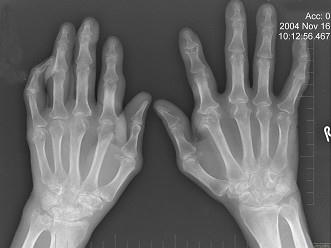

问题 男,72岁,手足多个小关节红肿热痛,并压痛明显,化验:白细胞升高,血沉增快,血尿酸升高,请结合所提供图像,选择最佳选项 ( )

选项 A、假痛风 B、滑膜炎 C、退行性骨关节病 D、痛风性关节炎 E、类风湿关节炎

答案 D